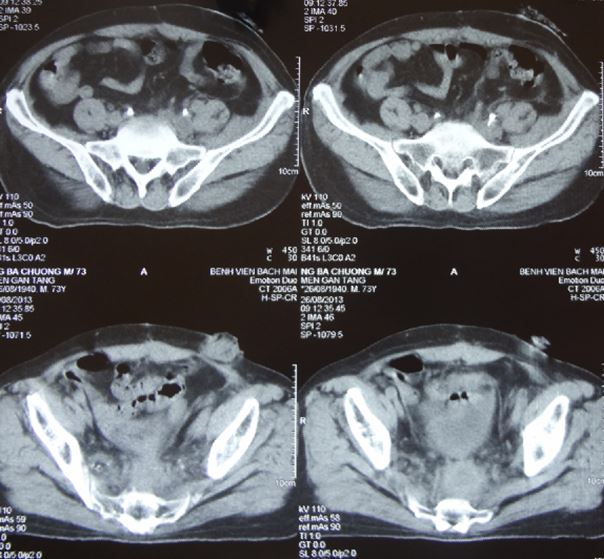

Trên hình ảnh cắt lớp vi tính ổ bụng: không có hình ảnh tái phát, di căn

Hình 3. Hình ảnh chụp cắt lớp vi tính (CT) ổ bụng